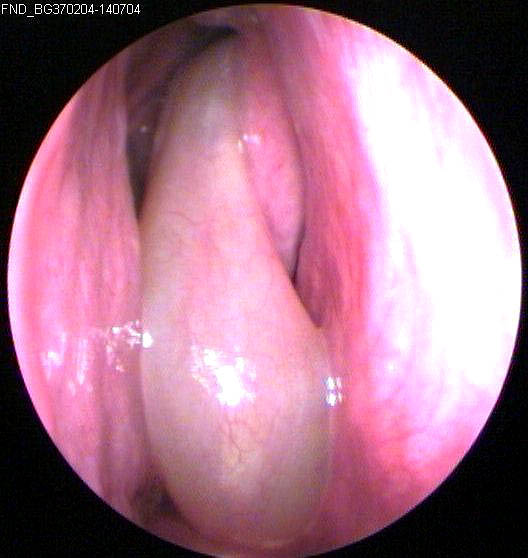

JFC Poliposis nasal bilateral.

JFC Poliposis nasal simple

JFC Poliposis nasal.